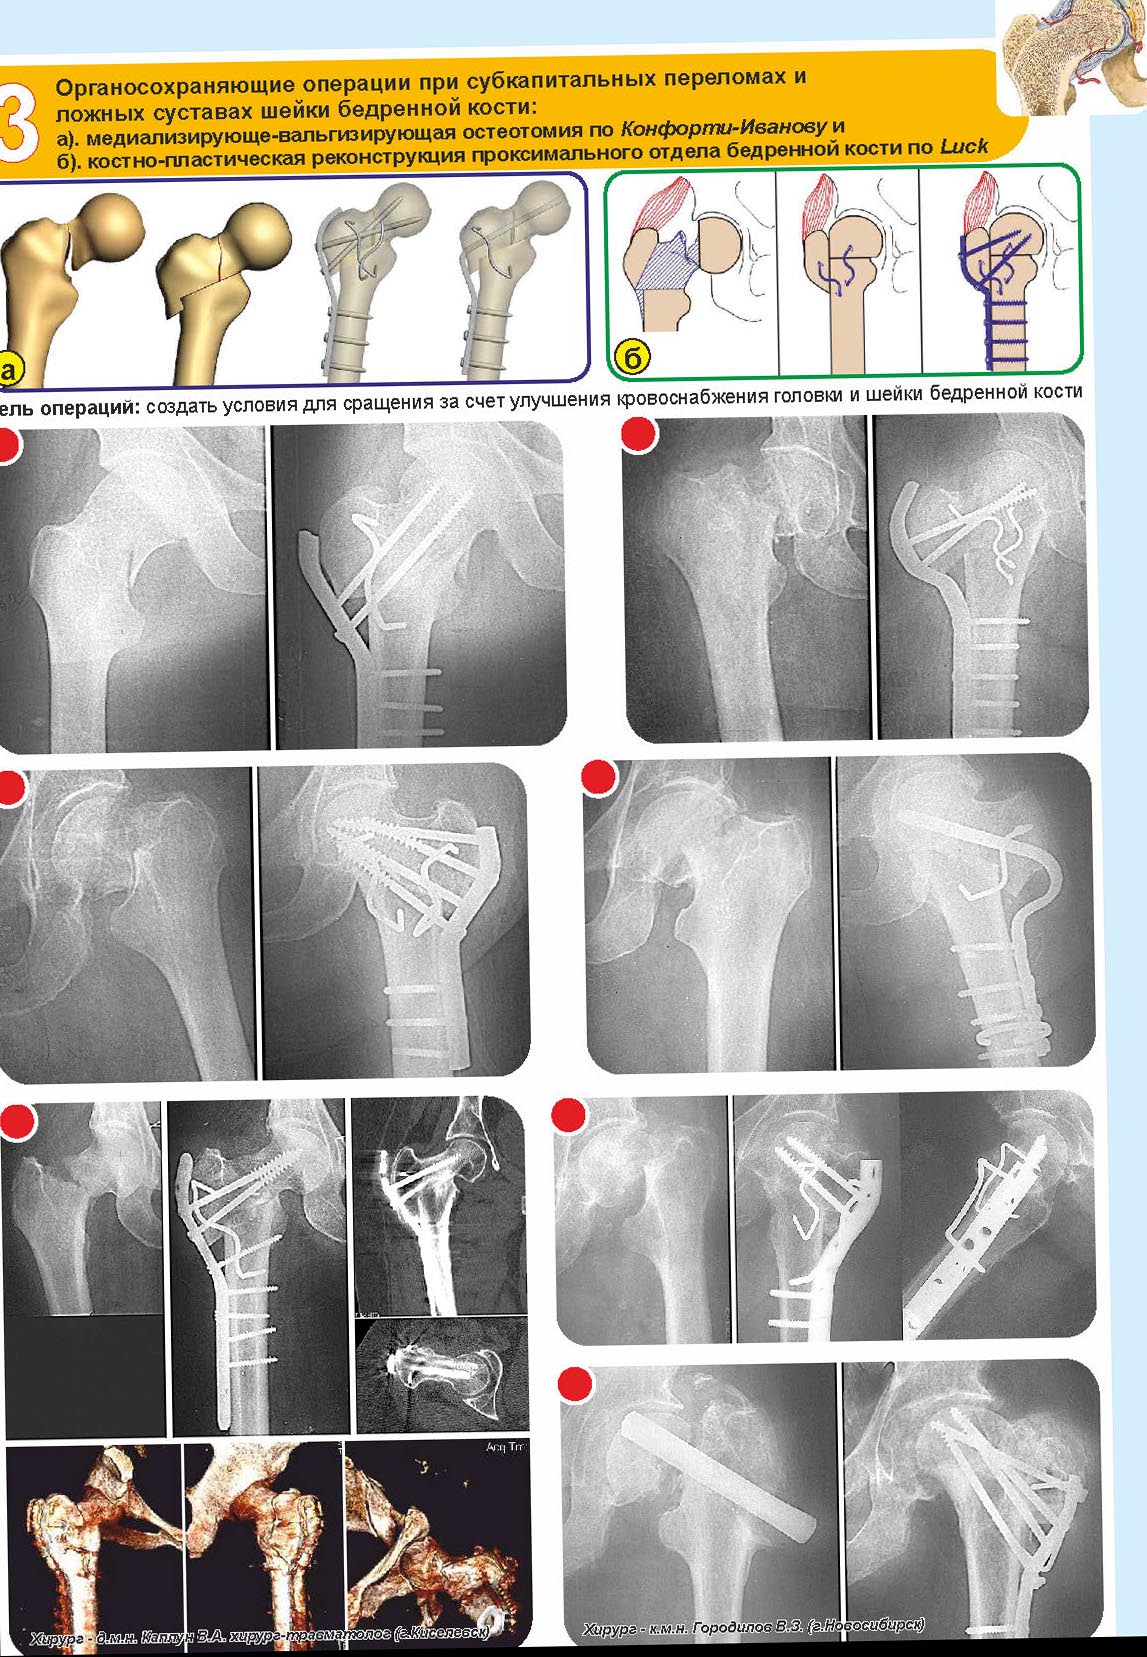

Imtamed 26 Ноябрь 2014, 10:43

Способы лечения